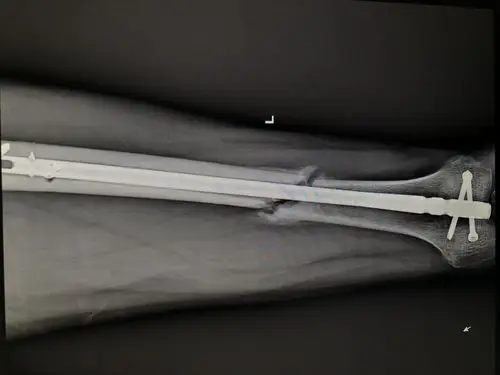

大腿骨折100天检查有少量骨痂.还会不会骨不连?

伤后34天的x线片,骨折端有大量骨痂形成.

术后6个月见少量骨痂

骨骨干骨折术后3个月骨折线模糊骨痂少.